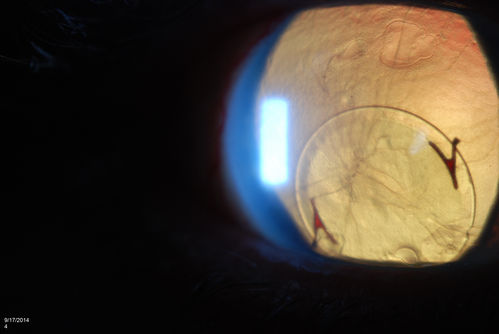

Free Floating Dislocated Lens in Vitreous

Patient comes in aphakic with dislocated lens floating to the back of the eye when laying down. Lens is laying up against the endothelium of the cornea when patient is right side up..

Mayo Clinic Jacksonville, Florida

TOPCON D-90 SL/NIKON